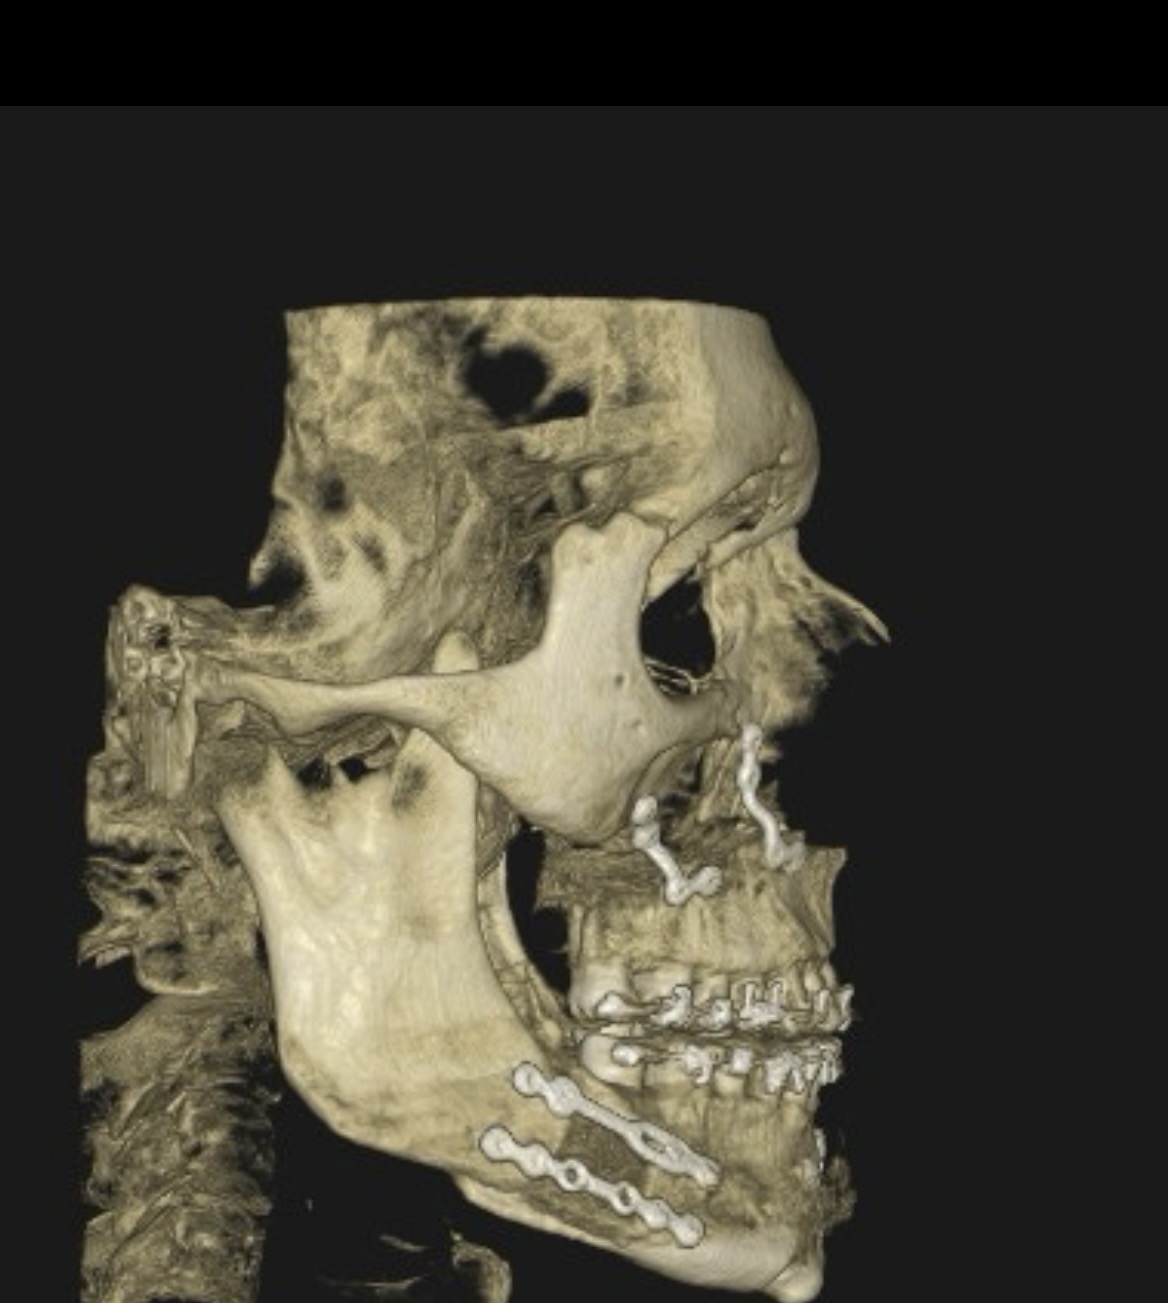

Barely felt her lips on mine the whole time cuz of nerve dmg but damn now iam not insecure about the post op swelling anymore